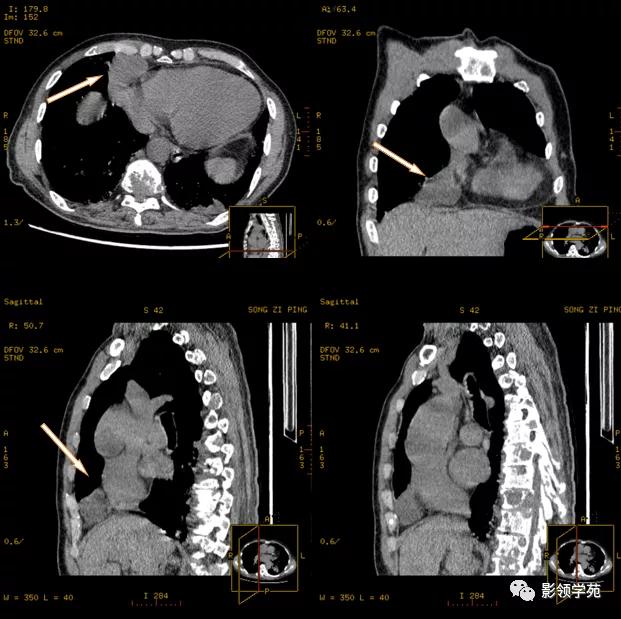

肿块周围脂肪间隙消失,与邻近结构分界不清

分叶状,边缘不规则,与邻近结构脂肪间隙消失